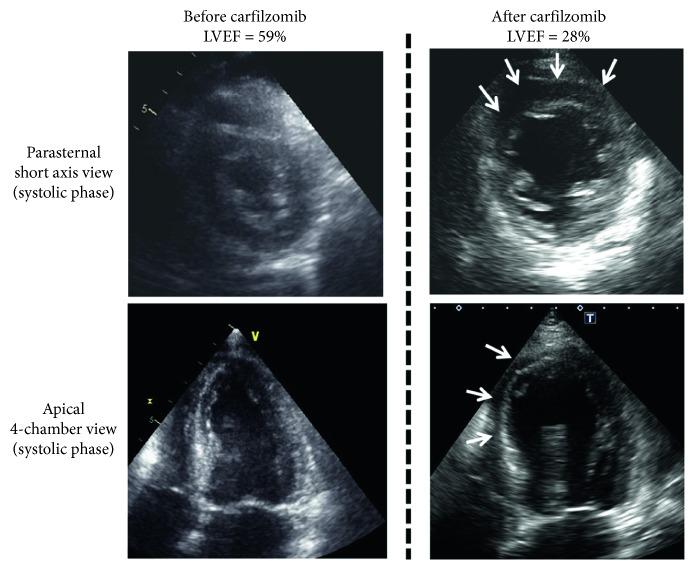

Carfilzomib (CFZ) improves progression-free survival for patients with relapsed or refractory multiple myeloma (MM) but has shown higher frequency of cardiovascular adverse events (CVAEs) than other proteasome inhibitors. We report the first autopsy case of acute death from cardiac failure shortly after administration of carfilzomib. A 74-year-old female was diagnosed with IgA MM after a 2-year period of smoldering MM. She was refractory to both bortezomib plus dexamethasone and lenalidomide plus dexamethasone therapies, so she subsequently received CFZ in combination with lenalidomide and dexamethasone. The day after the start of the therapy, she complained of severe dyspnea with a significant decline in left ventricular ejection fraction. Her acute cardiac failure rapidly progressed, and she died on day 7 of the start of CFZ. The autopsy showed invasion of inflammatory cells between the myocardial cells and very little myocardial necrosis. There was no obvious thrombus in the coronary artery of the heart, and no infarction or amyloid deposition was observed in the myocardium. Pathological findings of hypersensitivity myocarditis, a drug-induced cardiomyopathy, appeared to agree with this case except for absence of an eosinophilic infiltration of the myocardium. A CFZ-induced CVAE is generally considered reversible. However, rapidly progressing fatal heart failure like in our case is rare. To characterize CFZ-associated CVAE, further case collection is needed.

卡非佐米(CFZ)可改善复发或难治性多发性骨髓瘤(MM)患者的无进展生存期,但与其他蛋白酶体抑制剂相比,其心血管不良事件(CVAEs)的发生率更高。我们报告了首例在使用卡非佐米后不久因心力衰竭急性死亡的尸检病例。一名74岁女性在经过2年的冒烟型MM后被诊断为IgA MM。她对硼替佐米加地塞米松以及来那度胺加地塞米松治疗均无效,因此随后接受了CFZ联合来那度胺和地塞米松治疗。治疗开始后的第二天,她出现严重呼吸困难,左心室射血分数显著下降。她的急性心力衰竭迅速进展,并在开始使用CFZ的第7天死亡。尸检显示心肌细胞之间有炎性细胞浸润,心肌坏死极少。心脏冠状动脉无明显血栓形成,心肌未见梗死或淀粉样沉积。除心肌无嗜酸性粒细胞浸润外,药物性心肌病——过敏性心肌炎的病理表现似乎与该病例相符。CFZ诱导的CVAEs通常被认为是可逆的。然而,像我们病例中这样迅速进展的致命性心力衰竭很少见。为了明确CFZ相关的CVAEs特征,需要进一步收集病例。